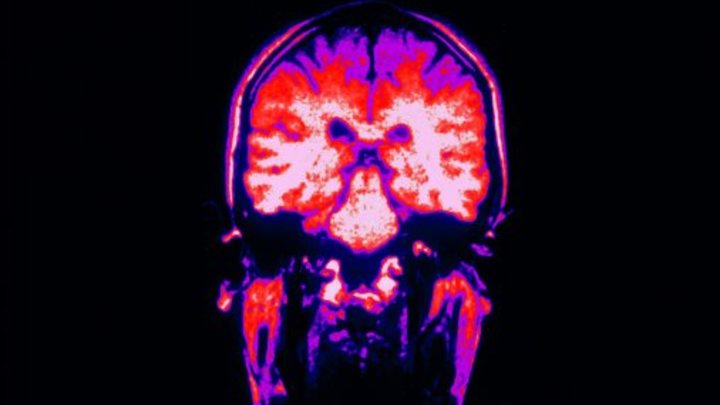

Учёные России работают над процессом выращивания нейронов мозга

По словам специалистов, новый метод будет полезен в медицинских исследованиях.

В Белгородском государственном университете разработали метод культивирования нейронов головного мозга. Благодаря работе учёных можно будет определять влияние нейротоксинов или нейропротекторов на интенсивность дыхания клеток.

Как передаёт "Газета.Ru", учёные из Белгорода разработали способ культивации первичной смешанной культуры нейронов гиппокампа 18-дневного эмбриона и новорождённого мелкого грызуна.

Метод также позволяет выявлять нарушения в работе митохондрий (органеллы, производящие энергию для клетки), участвующих в клеточном дыхании, и подбирать правильные условия для выращивания нейронов уже на начальных этапах дифференцировки клеток,

- делится результатами руководитель проекта, старший научный сотрудник лаборатории генетических технологий и генного редактирования для биомедицины и ветеринарии Марина Сорокина.

Метод будет полезен для проведения скрининговых доклинических исследований, а также при тестировании некоторых фармакологических субстанций.